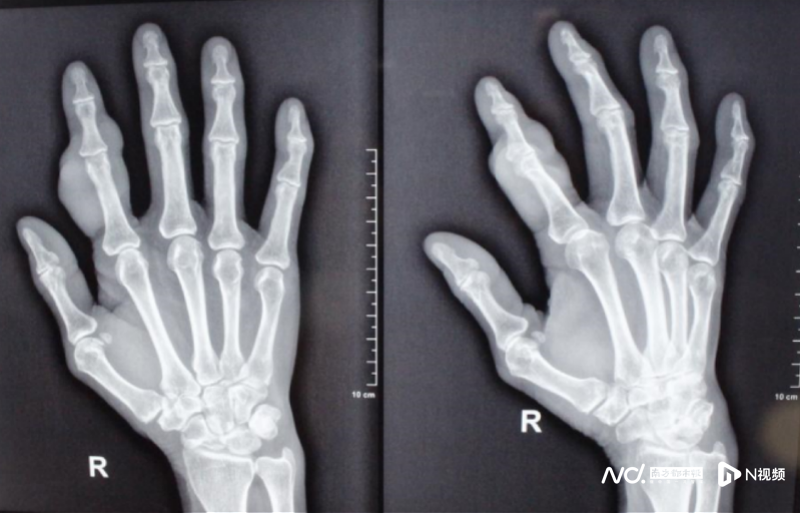

“患者來(lái)就診時(shí),在其指背及雙側(cè)可見大小不一腫塊,腫塊質(zhì)韌,活動(dòng)度差,影響指間關(guān)節(jié)活動(dòng)。初步診斷為腱鞘巨細(xì)胞瘤,術(shù)后病理報(bào)告也明確了這一診斷。”醫(yī)院顯微手外一科、手病?仆跣×⒅魅握f(shuō)。

術(shù)后食指外形恢復(fù)正常